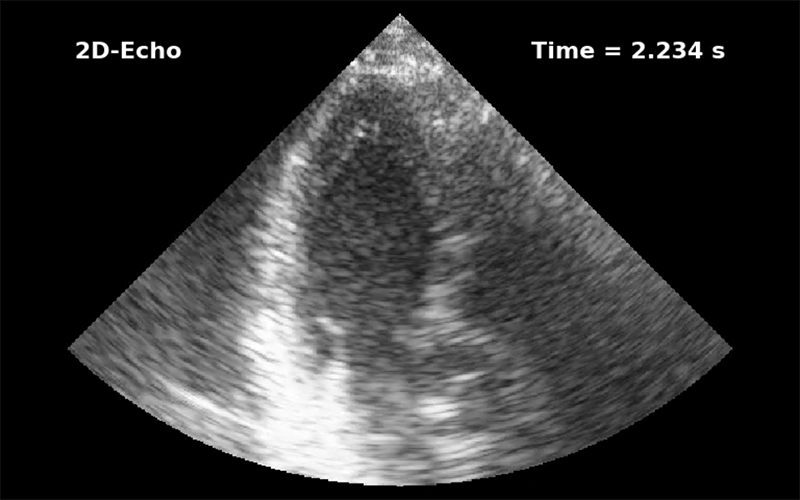

Veocor has developed the first cloud-based tool to diagnose the risk of cardiac thrombus formation and associated stroke. Veocor’s AI-powered technology quickly analyzes standard ultrasound images to provide a measure of blood flow in the left ventricle and identify regions at risk of thrombus formation. No additional hardware or training is required: cardiologists will be able to risk-stratify patients and identify who would benefit from anticoagulation.